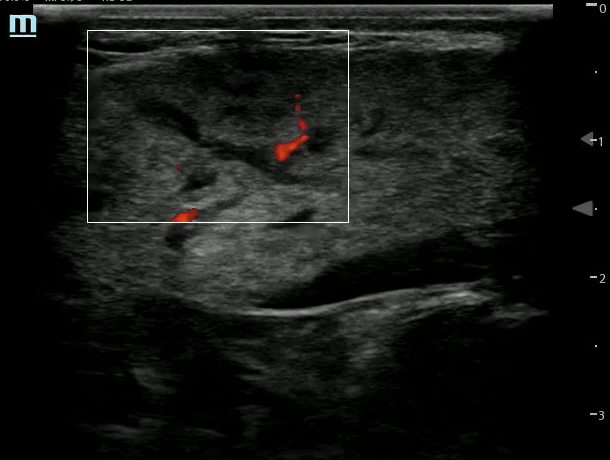

UVJ Stone with Left Hydro